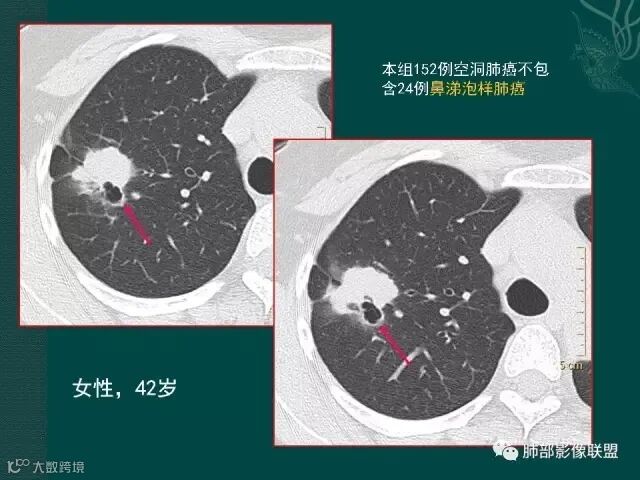

上一个是磨玻璃密度肺癌,边缘清晰,内有分隔,空洞型肺癌伴磨玻璃密度影的,100%为腺癌,很显然这是个假性空洞;

下一个也是肺癌,内有分隔,外下缘箭头所示也是磨玻璃影,这也是腺癌,同时可见叶间裂有转移灶。